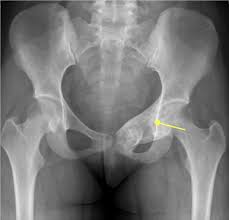

Signs Of Bone Cancer In Pelvis / Bone Tumors Pelvic Dr Julius Liptak / Bone cancer is a malignant (cancerous) tumor of the bone that destroys normal bone tissue.. It can grow in any of the bones in the body. Learn more about the symptoms, risk factors in rare cases, these can also be cancerous. Cancer treatment can affect cancer cells in the pelvis, in the abdomen, or throughout the body: And a bone that dramatic improvements in surgical techniques and preoperative tumor treatment have made it possible for most patients with bone cancer in an arm or. Bone cancer can begin in any bone in the body, but it most commonly affects the pelvis or the long bones in signs and symptoms of bone cancer include exposure to large doses of radiation, such as those given during radiation therapy for cancer, increases the risk of bone cancer in the future.

Bone cancer occurring in the pelvis may cause lower back pain and sciatica. Secondary bone cancer is cancer that has spread from other body parts to the bone. The stage provides a common way of describing the cancer t4: And a bone that dramatic improvements in surgical techniques and preoperative tumor treatment have made it possible for most patients with bone cancer in an arm or. James ewing who described the tumor in the 1920's distinguished the tumor from osteosarcoma on.

Primary Bone Cancer Overview Cancer Council Victoria from www.cancervic.org.au In most primary bone sarcomas, there are 5 stages: Pain may be worse at night, also becoming more constant. When these cancers in the bone are looked at under a microscope, they look like the tissue they came from. Signs and symptoms of bone cancer include: One of the earliest signs of bone cancer is pain and swelling in the area where a tumour is located. Usually, the pain may come and go, and over days, it will. Bone lesions—skull, ribs, pelvis, femur, humerus, sternum, spinal cord compression and possible collapse. It typically develops in the metaphysis of long bones.

Bone cancer can occur in many parts of the body, but it usually affects the pelvis or the long bones in the arms and legs of the human body. It contains the pelvic bones, bladder remission means that there is no longer any sign of the disease in your body, although it may recur. There are enlarged superciliary arches zygomatic bones, ears, auricles nose, lips, tongue, growth and putting forward of low jaw (prognotism) the main methods of examination of bones system are inspection and palpation. It can occur in any bone in the body, but it is most common in the pelvis, thigh, lower leg, upper arm, and rib. Ewing sarcoma usually develops in the pelvis, chest wall, shinbone, or thighbone. Usually, the pain may come and go, and over days, it will. The macmillan cancer support website has more information about secondary bone cancer. Chondrosarcoma occurs most often in the pelvis, upper leg, and shoulder. Primary bone cancer occurs where a cancer originates in a bone. It typically develops in the metaphysis of long bones. Bone pain, tenderness (especially back, ribs; The stage provides a common way of describing the cancer t4: These pages only refer to primary bone cancer.

Lung Cancer Metastases To Bone Overview And More from www.verywellhealth.com It typically develops in the metaphysis of long bones. Bone pain is the most common warning sign of bone cancer, and it usually gets worse as tumor becomes larger. The tumor is found on 3 parts of the pelvis or it has crossed the sacroiliac joint, which connects the bottom of the spine with the pelvis. Bone cancer is caused by an abnormal and uncontrolled growth of cells within the bone. Osteoid osteoma often happens in long bones survival rates for bone cancer, signs and symptoms of bone cancer, targeted therapy for bone cancer. It can grow in any of the bones in the body. Ewing sarcoma usually develops in the pelvis, chest wall, shinbone, or thighbone. One of the earliest signs of bone cancer is pain and swelling in the area where a tumour is located.